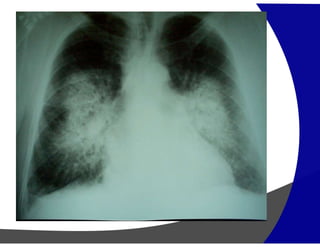

Sarcoidose

Definicao: doença granulomatosa nao-caseosa que acomete

um ou mais orgãos ainda com etiologia desconhecida,

todavia aspectos inflamatorios auto-imunes e infecciosos

podem estar associados.

•Pulmão e o tecido linfático são os órgãos mais

frequentemente acometidos

• Pacientes jovens com 20 a 40 anos

• O sintomas são leves ate a fase terminal

•O diagnóstico muitas vezes e incidental

ESTÁGIOS DA SARCOIDOSE

• 0 – nao tem alteraçoes

• 1 – adenopatia hilar e paratraqueal

(ocorre em algum momento em ate 90% casos)

• 2 – Adenopatia com envolvimento do parenquima

Infiltrado reticular

reticulonodular

miliar

nodulos maiores

Obs: sarcoidose alveolar?

•3 – Envolvimento do parênquima sem adenopatia

•4 – Alteraçao fibrosa que evolui para insuficiência pulmonar

Achados a TCAR:

• pequenos nodulos (INCLUSIVE SUBPLEURAIS)

• infiltrado peribronquiovascular e apicais

• infiltrado reticular intraobular e subpleural

Achados atípicos:

• grandes nodulos

• lesões cavitadas (degeneração isquêmica dos granulomas

associados)

Sarcoidose Definicao: doença granulomatosanao-caseosa que acomete um ou mais orgãos ainda com etiologia desconhecida, todavia aspectos inflamatorios auto-imunes e infecciosos podem estar associados. •Pulmão e o tecido linfático são os órgãos mais frequentemente acometidos • Pacientes jovens com 20 a 40 anos • O sintomas são leves ate a fase terminal •O diagnóstico muitas vezes e incidental

ESTÁGIOS DA SARCOIDOSE •0 – nao tem alteraçoes • 1 – adenopatia hilar e paratraqueal (ocorre em algum momento em ate 90% casos) • 2 – Adenopatia com envolvimento do parenquima Infiltrado reticular reticulonodular miliar nodulos maiores Obs: sarcoidose alveolar? •3 – Envolvimento do parênquima sem adenopatia •4 – Alteraçao fibrosa que evolui para insuficiência pulmonar

Achados a TCAR: •pequenos nodulos (INCLUSIVE SUBPLEURAIS) • infiltrado peribronquiovascular e apicais • infiltrado reticular intraobular e subpleural Achados atípicos: • grandes nodulos • lesões cavitadas (degeneração isquêmica dos granulomas associados)